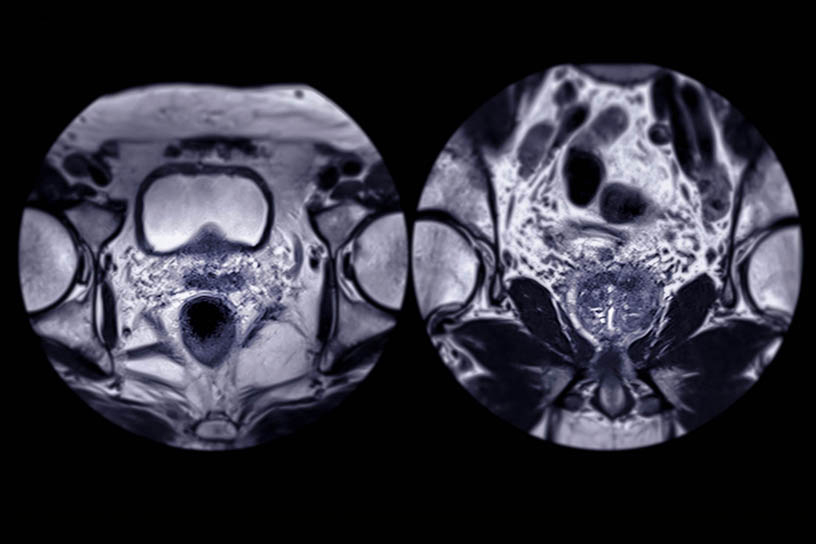

Während der Untersuchung werden verschiedene hochauflösende Bildsequenzen aufgenommen, die unterschiedliche Gewebeeigenschaften der Prostata darstellen. Die Kombination dieser Bildinformationen wird als multiparametrische MRT bezeichnet.

Die drei zentralen Bildkomponenten der mpMRT

Morphologische Bildgebung

(T2-Sequenzen)

Diffusionsbildgebung

Perfusionsbildgebung

(dynamische Kontrastmitteluntersuchung)